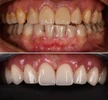

Zirkonyum uygulamalar

Porselen uygulamaları

Laminate veneer